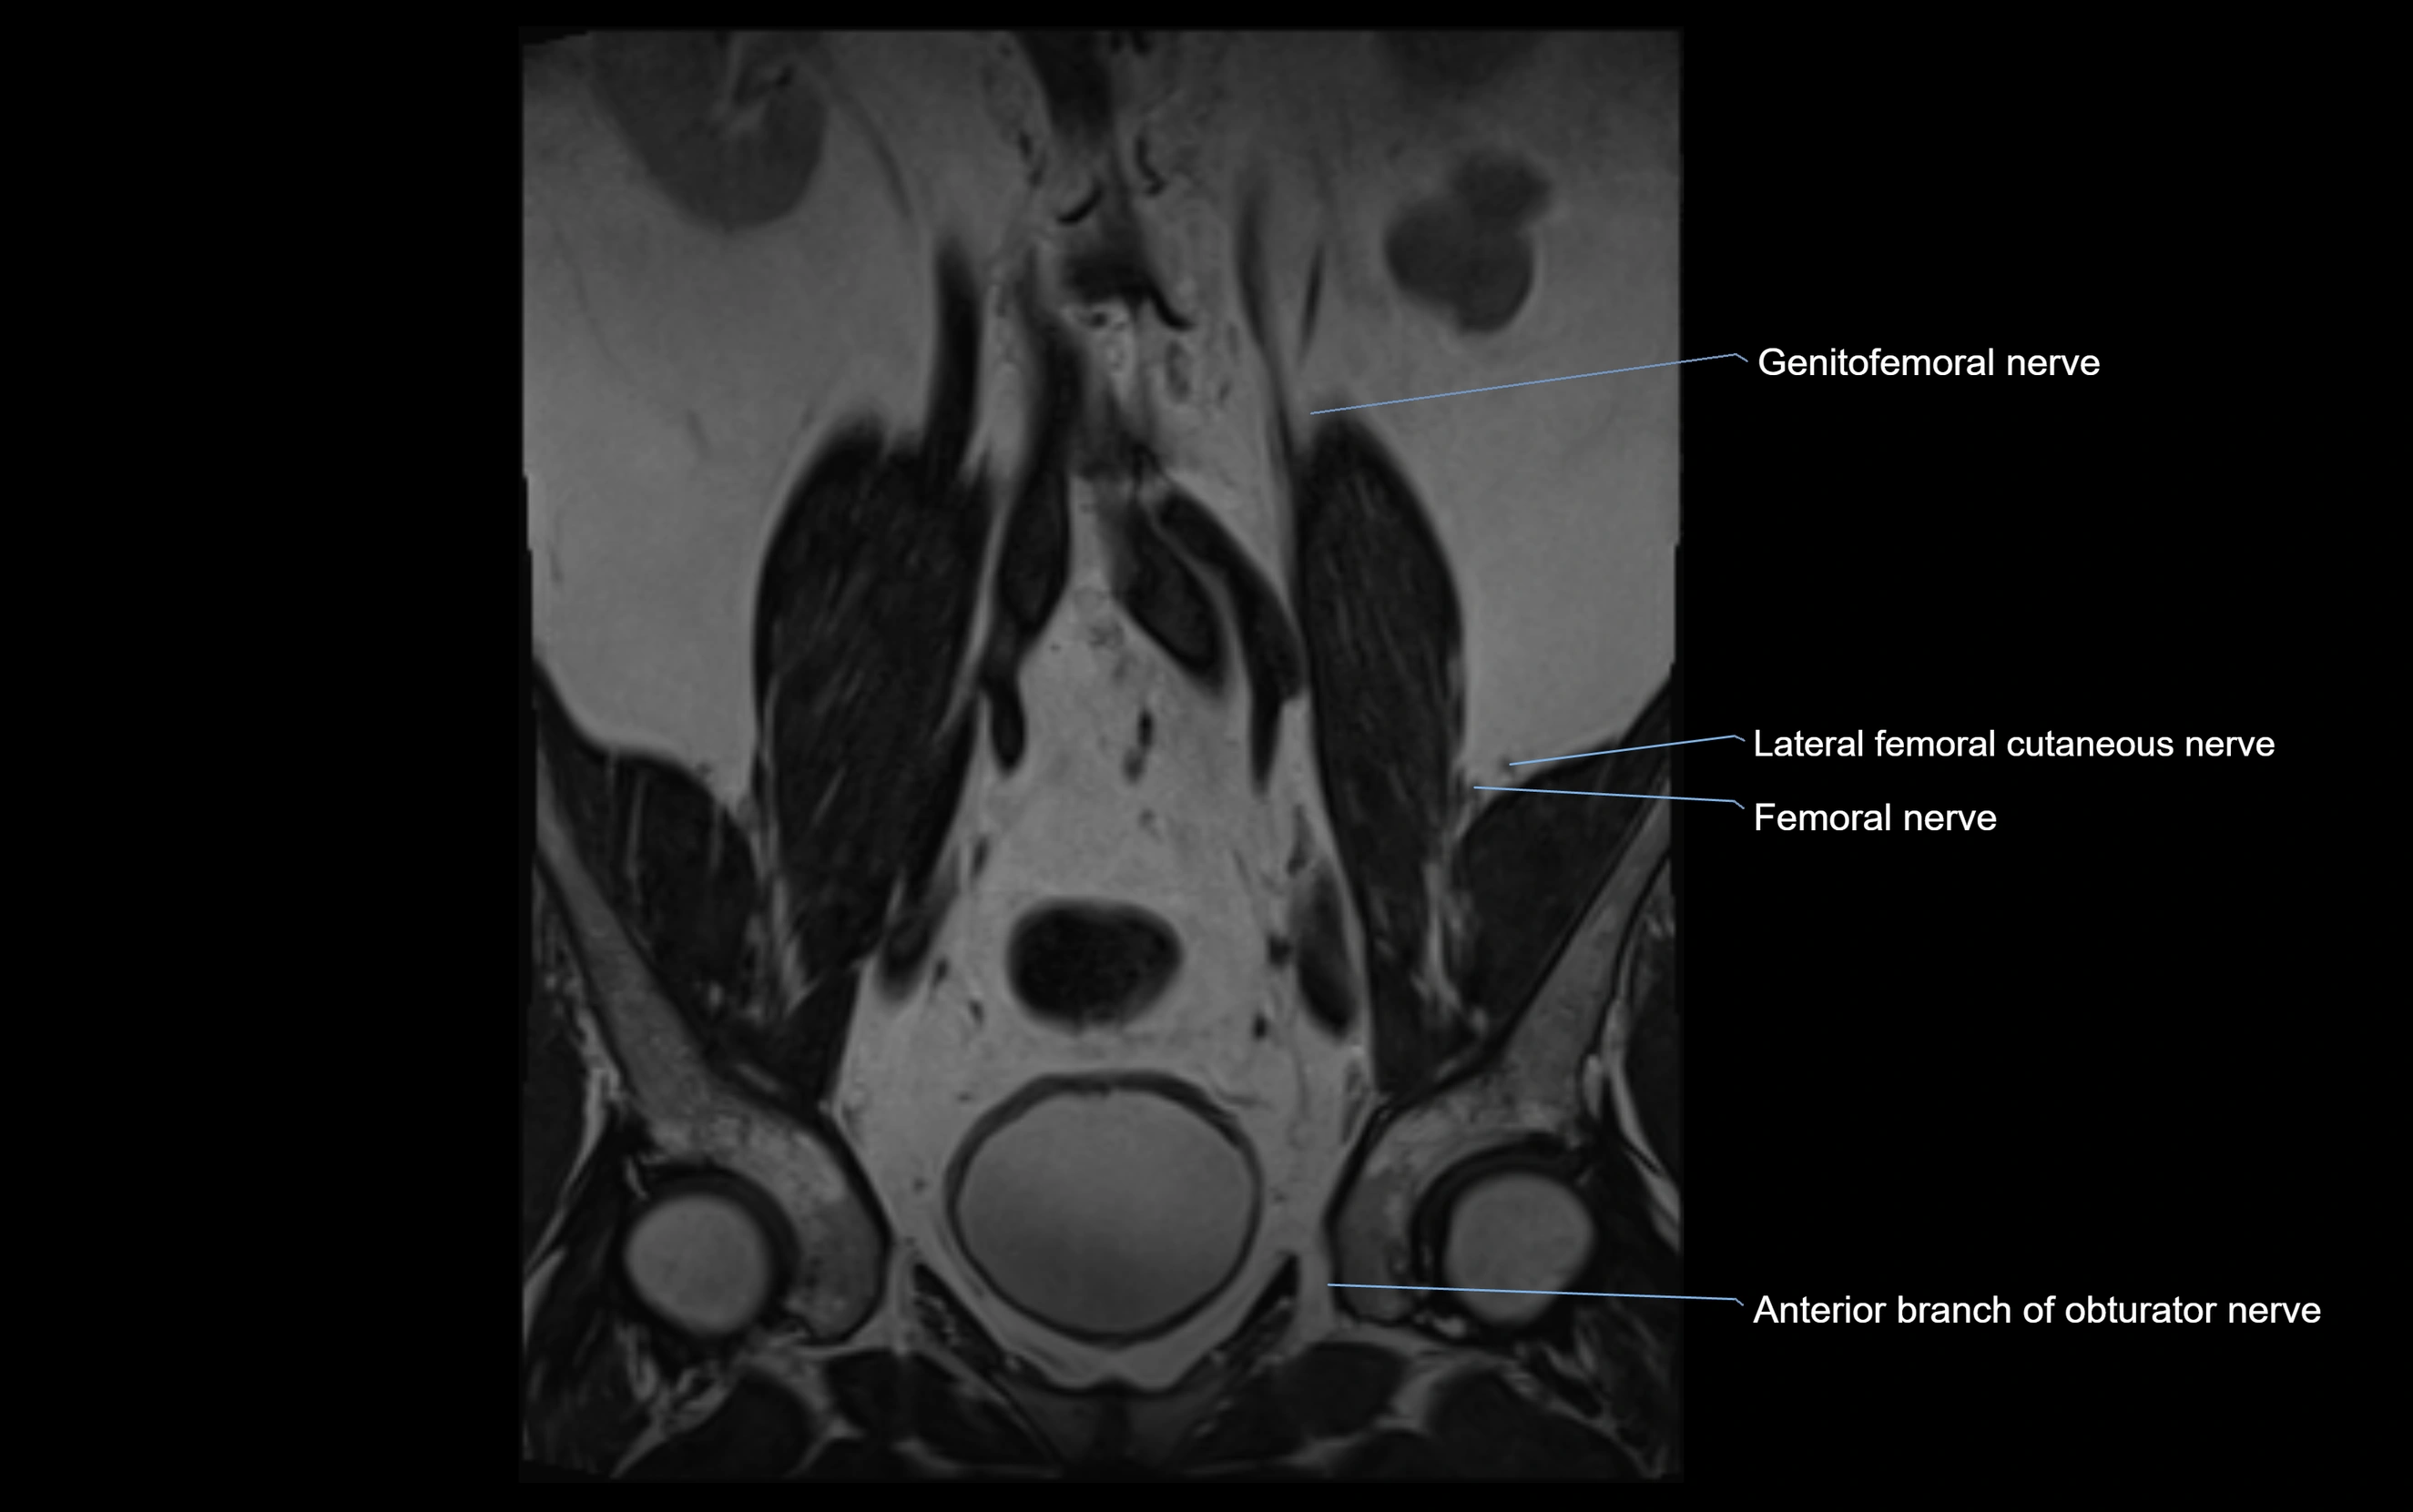

MRI image

image